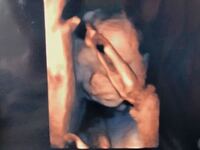

医師監修 妊娠19週のエコー写真 胎動をはっきりと感じられる時期 マイナビ子育て